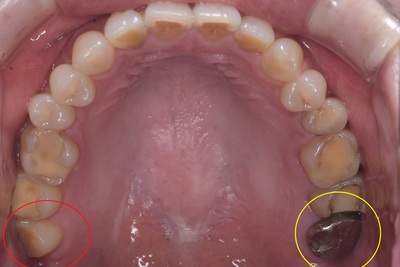

親知らずの抜歯症例

- 抜歯前の口腔内写真(上)

| 年齢 | 50代・女性 |

|---|---|

| 主訴 | 右上と左上下の親知らず |

| 親知らずの生え方 | 真っ直ぐに生えている |

| 抜歯時間 | 説明、麻酔含め各約30分 |

| 費用 | 各約1,240円(保険診療3割負担) (2024年12月現在) |

| 抜歯内容 | 抜歯後の負担を考慮して、右上、左上、左下の順で日にちを分けて抜歯しました。 |

| 治療方針 | 親知らずの手前の7番の虫歯治療が必要なため、先に虫歯になっている親知らずの抜歯から始めました。 |

| 担当者所見 | 左上親知らずは、メタルの被せ物が抜歯の際に外れ、中は虫歯で歯が溶けていました。 右上、左下もレジンのような材料で治療した痕がありましたが、いずれも大きく欠けており、歯として機能していませんでした。 |